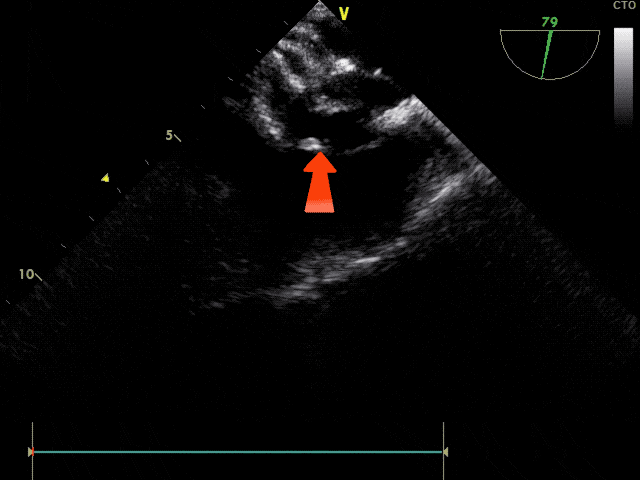

右盘展开

固定钢缆,后撤鞘管,展开右盘

轻推钢缆,使右盘成型

锁定前观察

锁定前观察,确认封堵器骑跨于房间隔两侧,稳固夹持